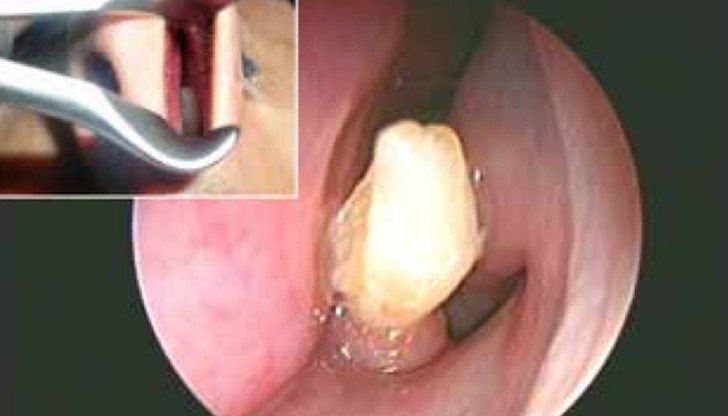

Лекарите са открили зъб в носа на мъж от Саудитска Арабия. Той страдал от постоянно течение на кръв от носа. След хилядите прегледи и изследвания медиците разбрали, че в обонятелния му орган расте не какво и да е, а истински зъб, пише Metro, цитиран от iNews.bg.

22-годишното момче имал проблеми с носа си всеки месец в продължение на 3 години. Накрая лекарите след много прегледи разбрали, че има зъб, който го драска от вътрешната страна на ноздрата и това причинява кървенето.

Лекарите били много изненадани от откритието тъй като момчето имало перфектен набор от зъби в устата си. След проведена операция зъбът, който измъчил момчето е премахнат.